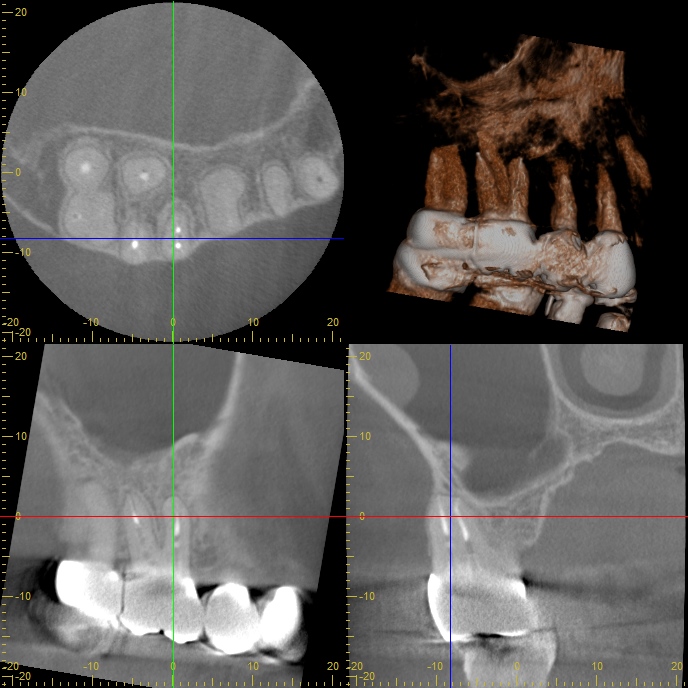

はじめに インプラント治療後の長期経過観察は、治療の成功を評価する上で非常に重要です。今回、8年前にインプラント治療を行った40代女性患者さんが、前歯の違和感を主訴に来院されました。この症例を通じて、長期経過症例における対応と、患者さんとのコミュニケーションの大切さについて考えていきたいと思います。 患者背景と初診時の状況 患者さんは40代女性で、医療系の職 …